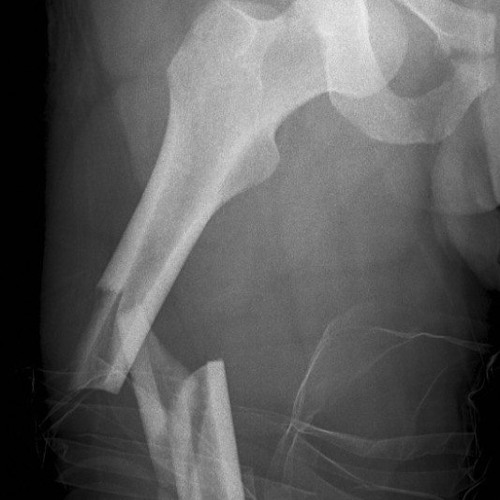

Фрактуры бедренной кости: лечение и восстановление

Раздел: Фотоколлекция